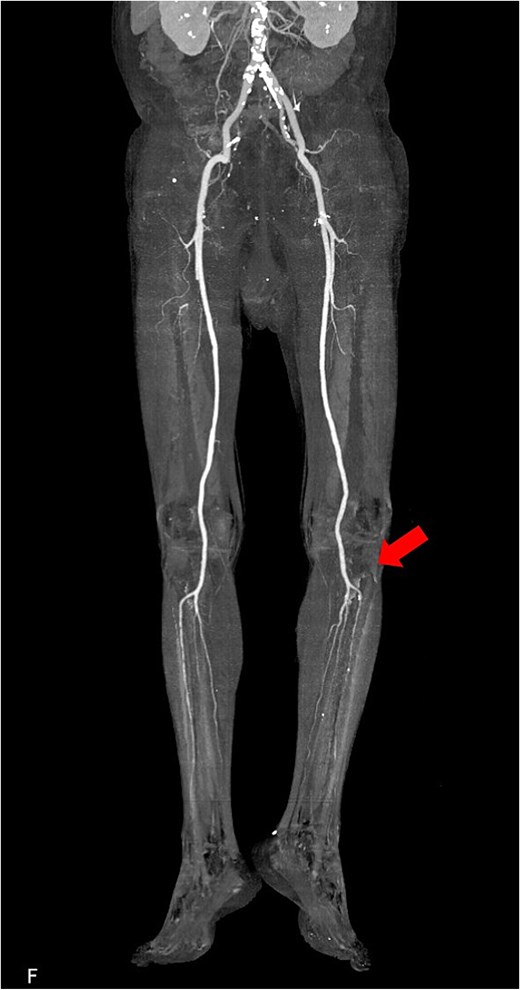

The patient was a 78-year-old man who had been hospitalized at a prior institution for Tolosa-Hunt syndrome, a rare inflammatory condition causing orbital pain. He had undergone steroid pulse therapy and was maintained on oral prednisolone (40 mg daily). He was also receiving medical treatment for diabetes mellitus, with an HbA1c level of 7.9%. The patient presented with complaints of left leg discomfort and weakness. Contrast-enhanced CT revealed poor perfusion distal to the left common iliac artery, leading to a diagnosis of ALI. He was subsequently transferred to our surgical department for further evaluation and treatment. On arrival, physical examination revealed coldness in the left lower limb, with absent palpable pulses in the dorsalis pedis and posterior tibial arteries. Doppler ultrasonography confirmed the absence of arterial flow in the left lower extremity, consistent with critical ischemia. The patient's electrocardiogram showed sinus rhythm. A review of CT imaging showed thrombotic occlusion extending from the left common femoral artery (CFA) to the superficial femoral artery, with poor perfusion distal to the popliteal artery (Video 1) (Fig. 1). Additionally, a filling defect was identified in the distal aortic arch, consistent with a thrombus (Fig. 2a). The thrombus appeared pedunculated and was attached to the lesser curvature of the descending thoracic aorta distal to the left subclavian artery. It was considered highly mobile, posing a significant risk of embolization. No evidence of intracardiac thrombi was observed, and the DTAT was identified as the likely embolic source responsible for the ALI. Given the urgency of salvaging the ischemic limb, thrombus retrieval was prioritized, while simultaneous management of the embolic source was deemed equally critical to prevent recurrence. Open surgery was considered high-risk due to the patient’s age, diabetes, and chronic steroid use. As a less invasive alternative, we opted for TEVAR to immobilize the floating thrombus. During the procedure, bilateral CFAs were surgically exposed to provide access and enable immediate removal of the embolic source if needed. A transesophageal echocardiogram (TEE) revealed a highly mobile intra-aortic thrombus (Video 2). A 26× 26 × 150 mm stent graft (Valiant Captivia Thoracic Stent Graft; Medtronic, Santa Rosa, CA, USA) was deployed just distal to the left subclavian artery under fluoroscopic guidance. Real-time TEE guidance ensured continuous monitoring of the floating thrombus and confirmed no embolization during intravascular manipulation. Following stent graft deployment, thrombus retrieval was performed via the left CFA using a 4-Fr Fogarty catheter (Fogarty Fortis arterial embolectomy catheter; Edwards Lifesciences, Irvine, CA, USA), successfully retrieving fibrin thrombi. Intraoperative angiography demonstrated restored blood flow in the lower extremity, with improved perfusion extending to the foot. Pulses in the dorsalis pedis and posterior tibial arteries were palpably restored bilaterally. The patient was extubated in the operating room and progressed without any findings suggestive of intestinal or lower extremity ischemia. Postoperative CT confirmed successful exclusion of the aortic thrombus (Fig. 2b) and restoration of adequate lower limb perfusion (Fig. 3). The patient was initiated on oral anticoagulation therapy with edoxaban 30 mg to prevent future thrombus formation and experienced an uneventful recovery. This patient has remained free of recurrent embolic events and has shown stable progress post-procedure.

Preoperative 3D reconstructed contrast-enhanced CT. No contrast effect is seen in the blood flow of the lower leg.

Postoperative 3D reconstructed contrast-enhanced CT. The contrast effect on lower limb blood flow is good.